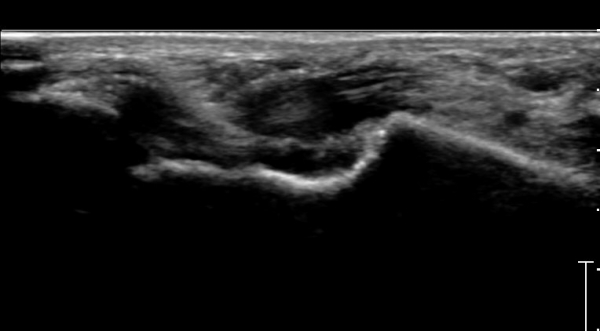

ÇϺΠ½ÅÀü ¶ì(inferior extensor retinaculum) ÀÇ frondiform Àδë Á¾´Ü¸é°Ë»ç¿¡¼­

frondiformÀÎ´ë ½ÉºÎ°¡Áö ÁÖº¯ ¼ö¾×Àú·ù°¡ °üÂûµÇ°í Á·±Ùµ¿ °æºÎÀδ밡 ³Ê¹« ¶Ñ·ÇÈ÷

°üÂûµÈ´Ù(»çÁø 5, 6, 7).